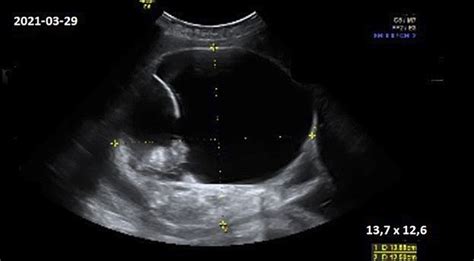

„Šį tyrimą jums gali atlikti jus prižiūrintis akušeris-ginekologas toje moterų konsultacijoje, kurioje jūs lankotės. Jeigu nėra jokių nukrypimų nuo normalios nėštumo eigos, to gali ir užtekti. Ultragarsinio tyrimo metu gydytojas akušeris-ginekologas tirdamas echoskopu įvertins, kiek yra vaisių, ar vaisius yra gyvas, pasakys, kur yra placenta, kiek yra vandenų. Taip pat įvertins vaisiaus anatomiją bei pamatuos patį vaisių. Tai yra labai svarbu vertinant nėštumo trukmę, patikslinant gimdymo datą“, - pasakoja docentė.

Antrasis ultragarsinis tyrimas nėštumo metu privalomas yra 18-20 nėštumo savaitės patikra arba vadinamoji antrojo nėštumo trečdalio ultragarsinė patikra. „Jos metu taip pat vertinama vaisiaus anatomija. Kadangi vaisius šiuo metu jau yra didesnis, mes atidžiai tiriame visas vaisiaus anatomines struktūras, vaisiaus smegenis, širdį, galūnes. Taip pat šio nėštumo metu, jeigu jūs pageidaujate, dažniausiai galime pasakyti ir vaisiaus lytį, nes dažnai moterys apie tai klausia. Šis laikotarpis yra turbūt vienas tiksliausių, kada galime tai įvardinti“, - sako gydytoja.

Šio ultragarso tyrimo metu labai svarbu dar kartą patikrinti nėštumo trukmę, įvertinti, kaip vaisius auga bei sudaryti tolimesnio nėštumo ir gimdymo priežiūros planą.